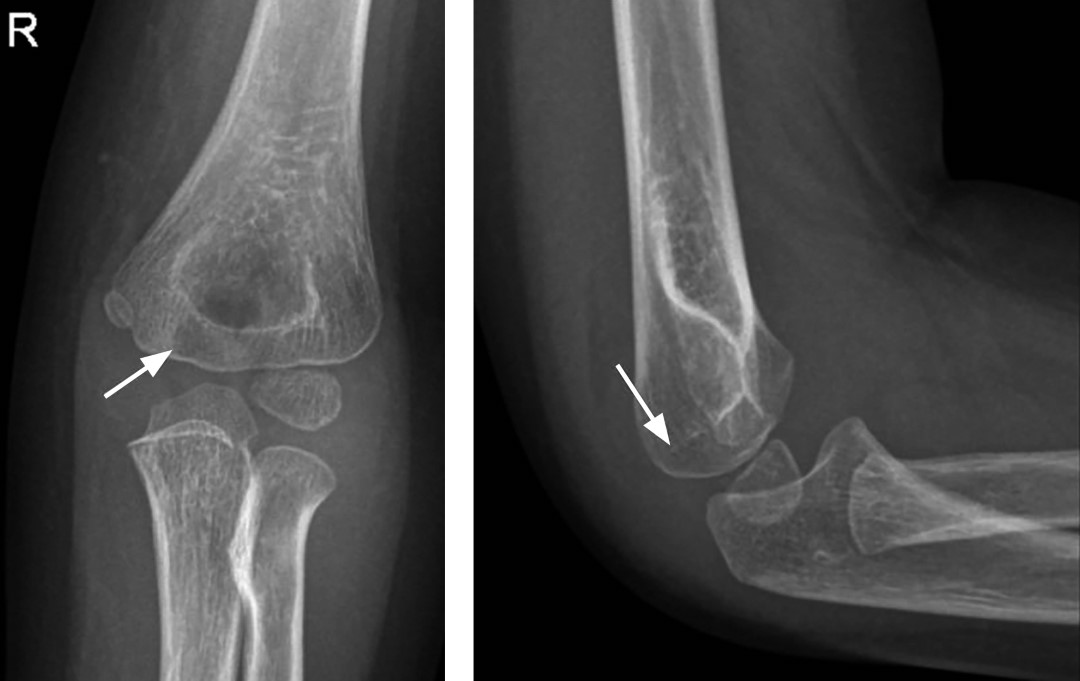

Figura 4